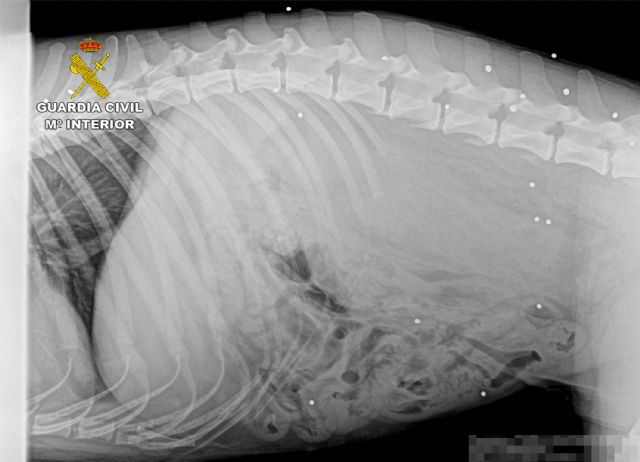

Las primeras pesquisas permitieron constatar que dos de los canes propiedad del denunciante habían sufrido heridas tras ser alcanzados por plomos de cartuchos de caza, según se apreciaba en el informe veterinario y radiológico, en gran parte de su cuerpo. Al parecer, había un tercer perro que aún sigue desaparecido y que se presume que también pudo haber sido alcanzado por los disparos.